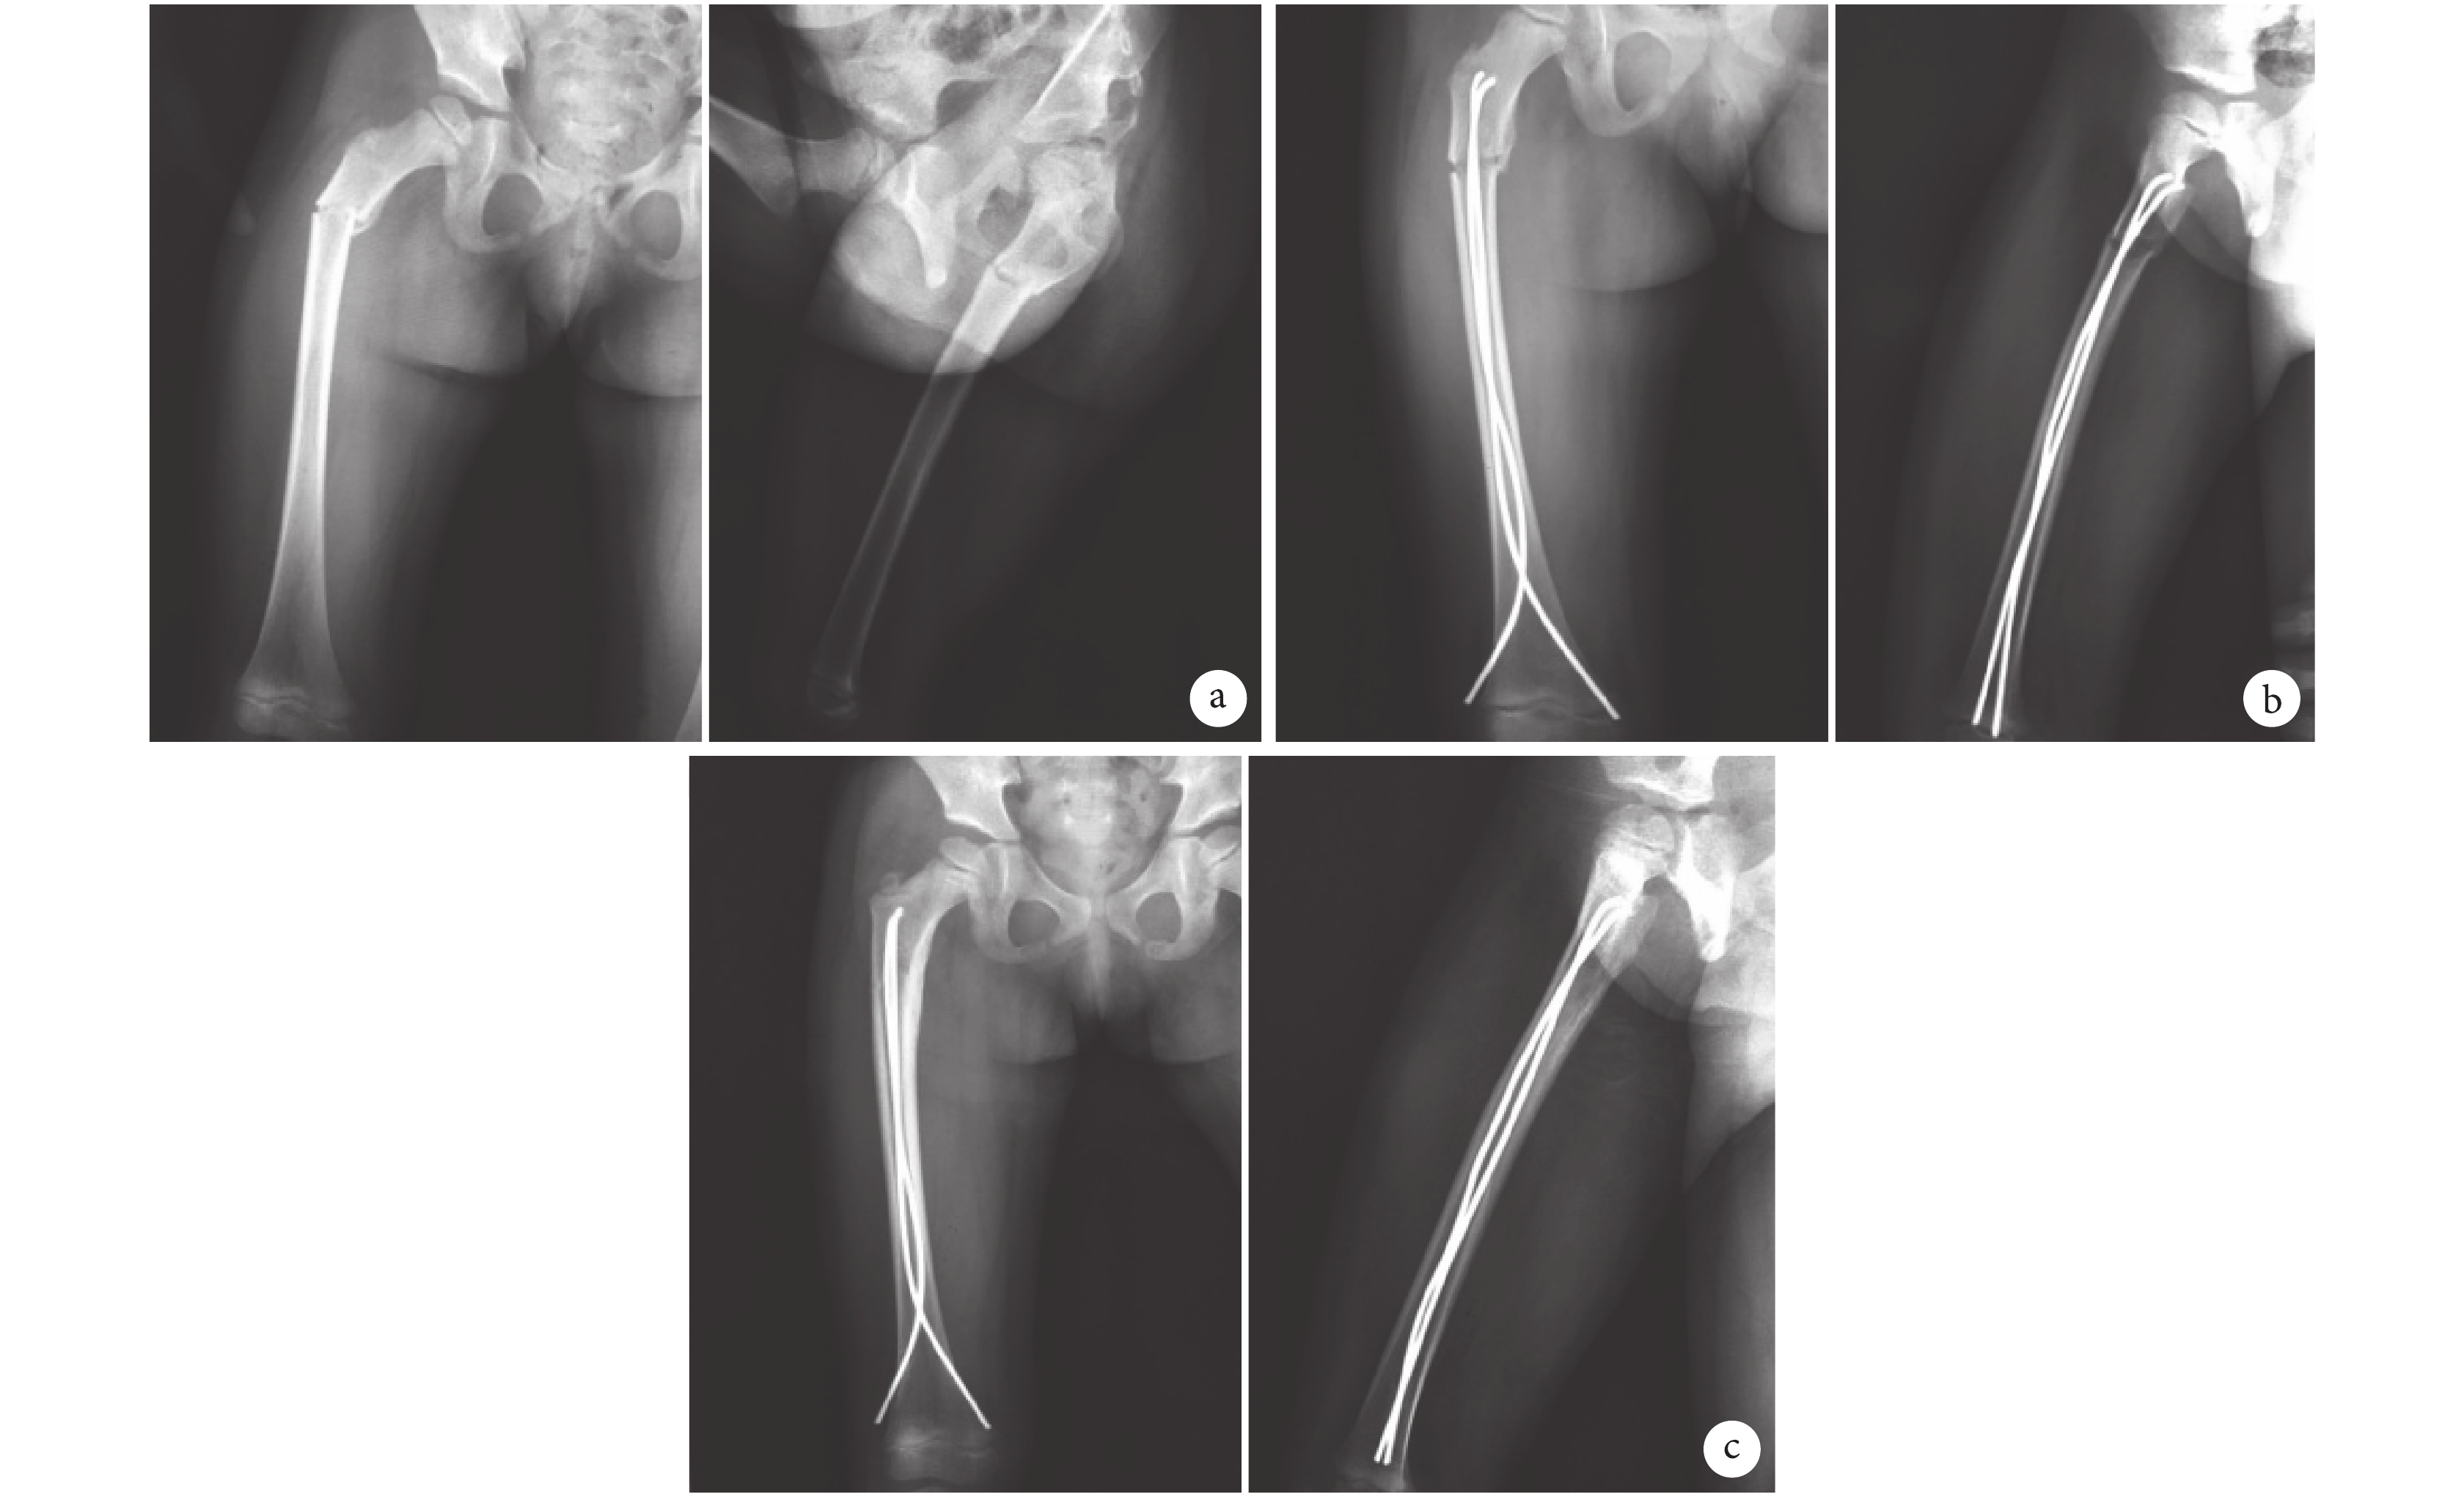

圖1

A 組患兒,女,7 歲,交通事故傷致右股骨粗隆下骨折(SeinshimerⅡ型)正側位 X 線片

a. 術前;b. 術后 1 d;c. 術后 6 個月

Figure1. Anteroposterior and lateral X-ray films of a 7-year-old girl with femoral subtrochanteric fracture (Seinshimer Ⅱ type) of the right lower limb caused by traffic accident in group Aa. Before operation; b. At 1 day after operation; c. At 6 months after operation